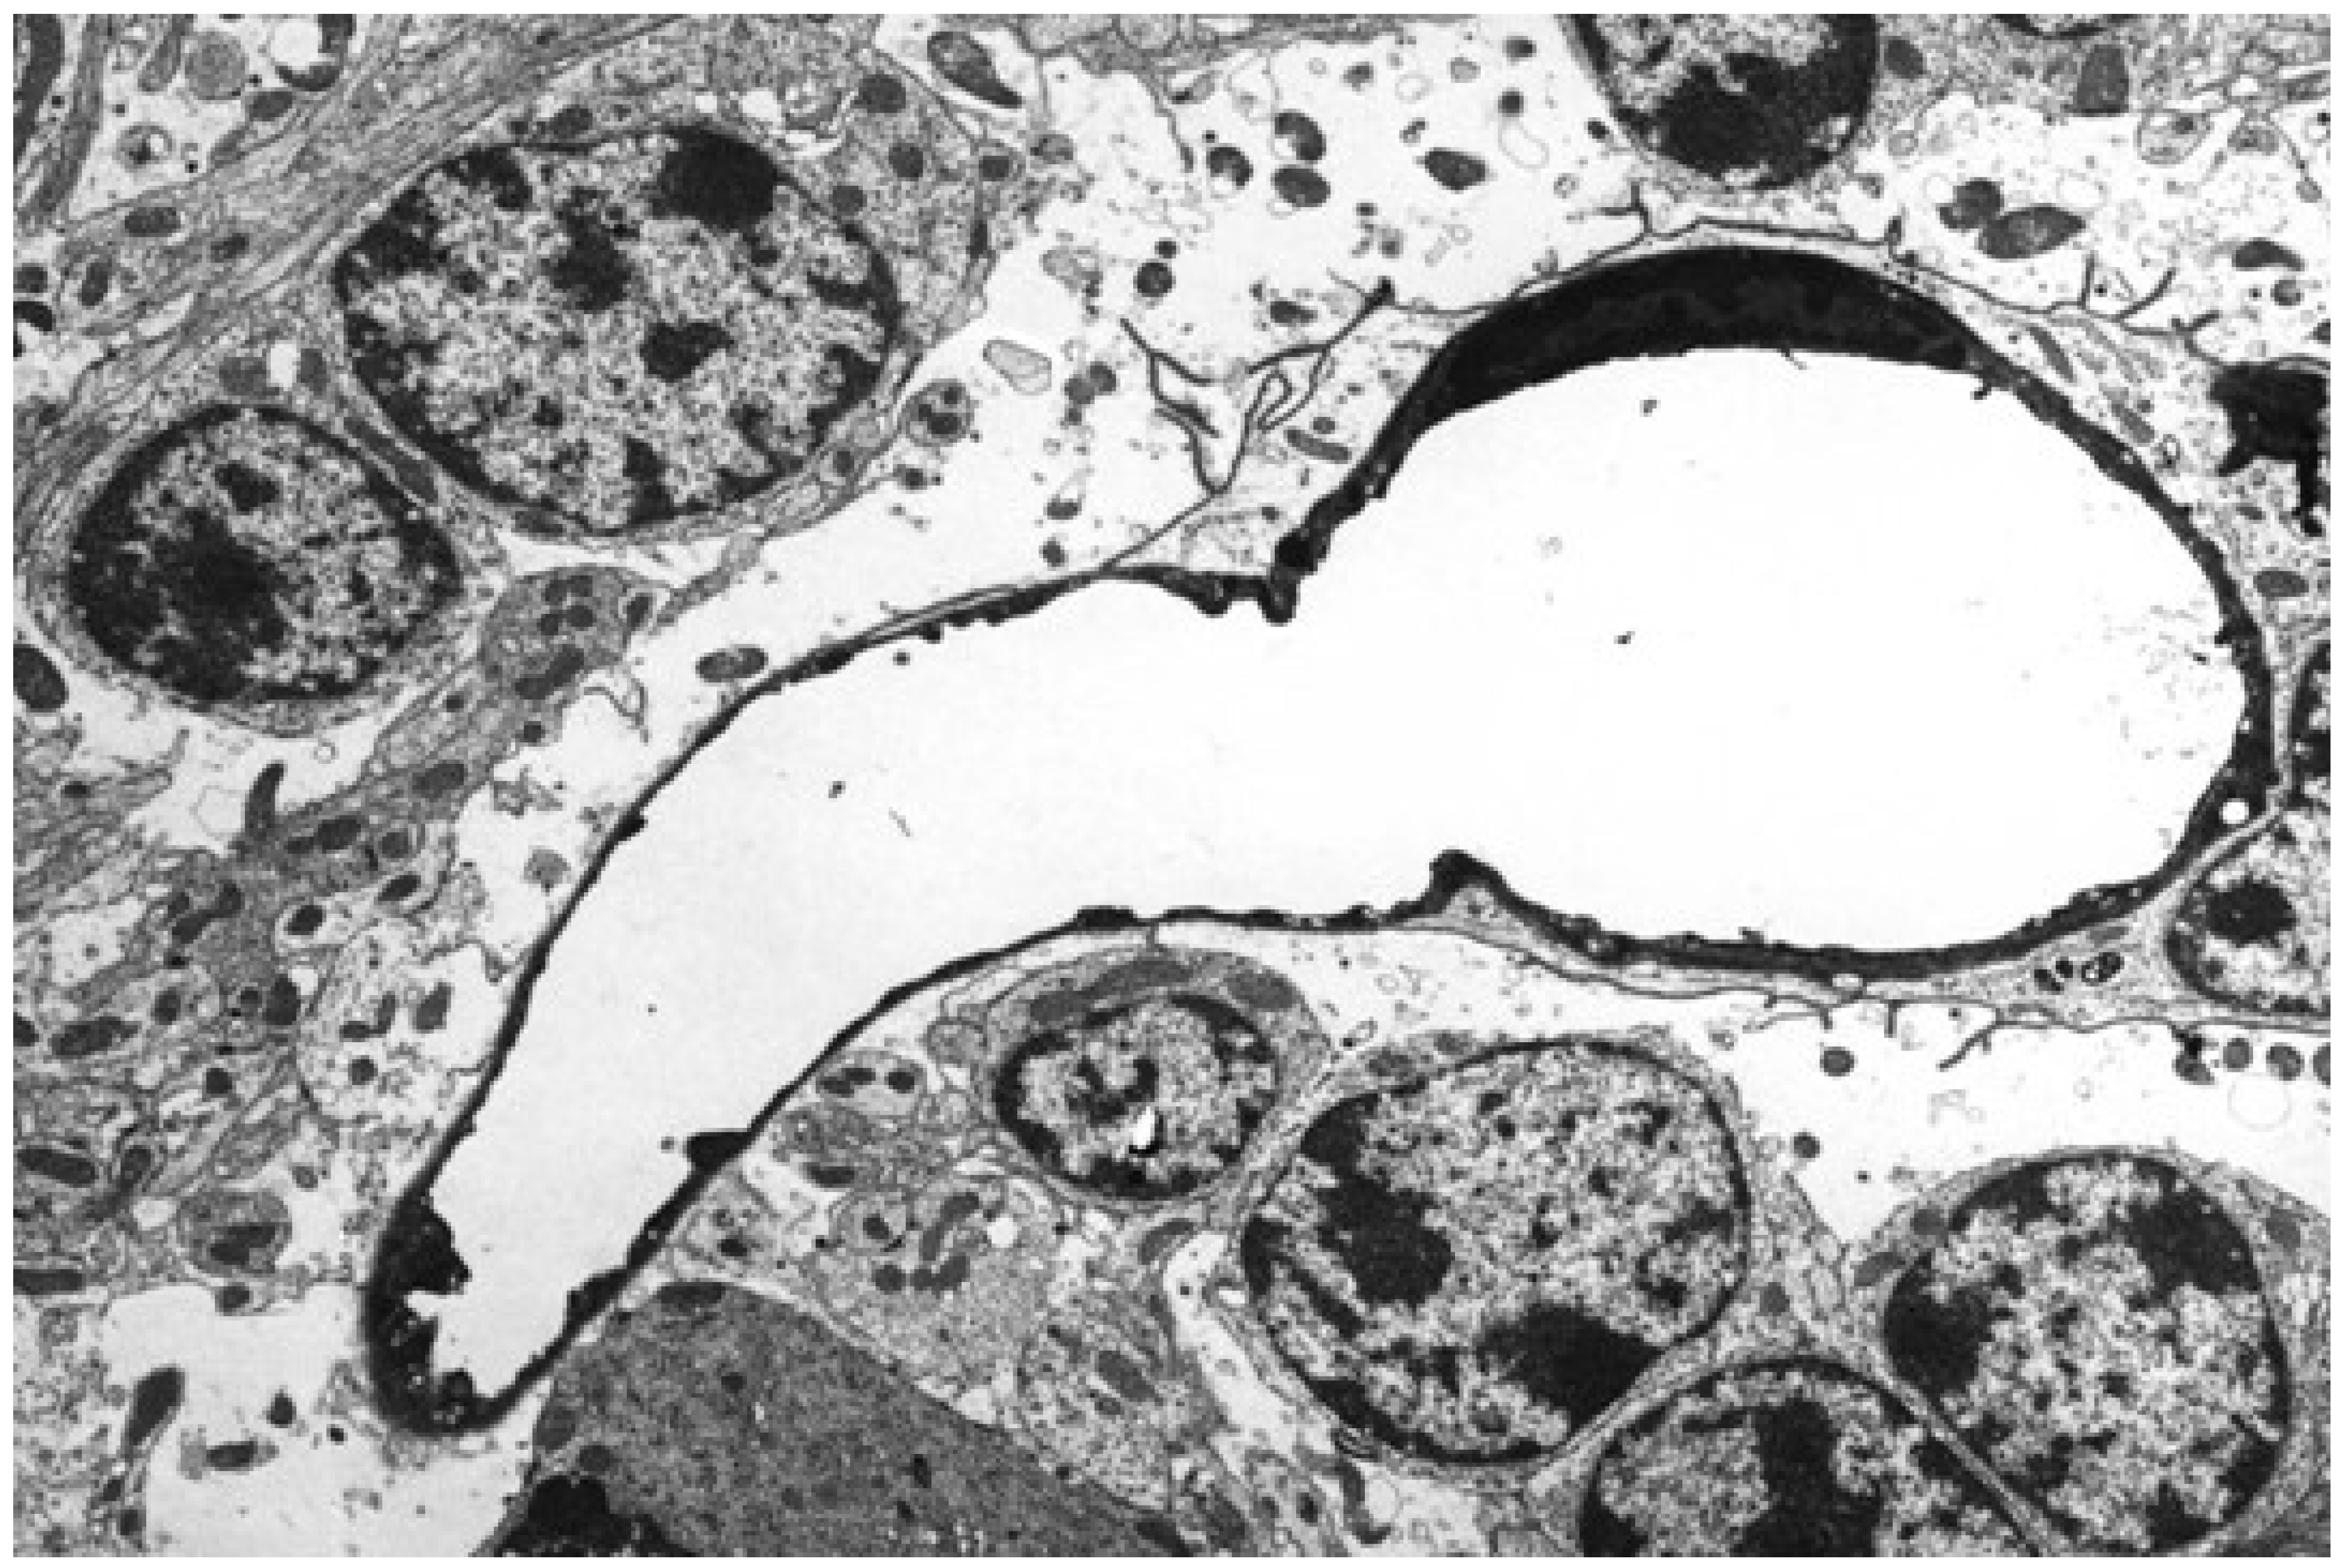

5.2. Neuropathology